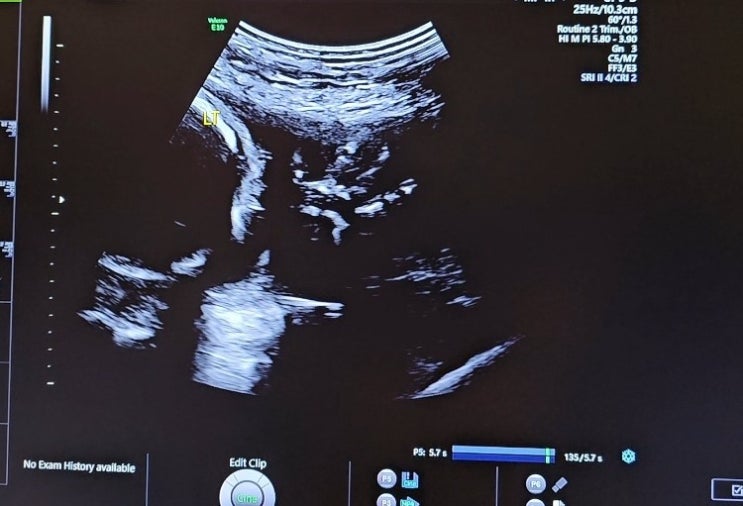

임신 23주 5일 초음파, 경부길이

2023.08.17. 세브란스 다녀온 지 벌써 2주! 지난번에도 경부길이가 조금 짧게 나왔기 때문에, 경부길이랑 ...